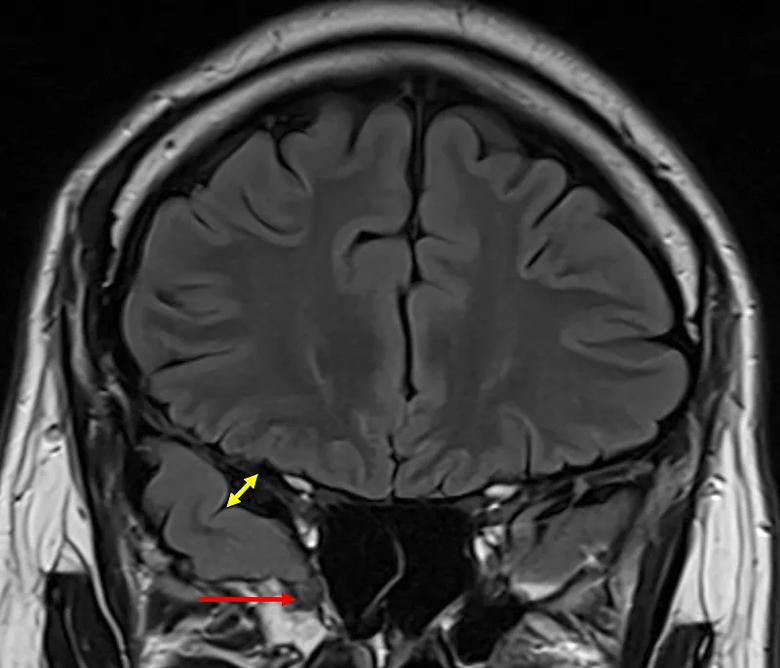

The results revealed a distinct imaging signature for encephaloceles. Specifically, the frontotemporal aperture was significantly wider on the side containing the lesion, particularly at the anterior edge of the temporal lobe. Moreover, the temporal opercular angle was significantly smaller on the affected side, creating a wider overall opercular angle difference.

Notably, these metrics remained significant even in the 26% of patients whose encephaloceles were missed during the initial preoperative MRI review. In contrast, the control group with mesial temporal sclerosis showed no significant asymmetries in frontotemporal aperture or opercular angle, suggesting that these changes are unique to the structural distortions caused by encephaloceles.

These findings support what the study authors call the tethering hypothesis. Surgeons often observe that the encephalocele acts as a physical anchor; even after the lateral cortex is disconnected, the brain tissue to be resected remains attached to the skull base until the lesion is released. The widened Sylvian fissure observed on MRI likely reflects the chronic rotational or traction forces exerted on the temporal lobe by this attachment point.

brain MRI with a red arrow and double-sided yellow arrow

MRI showing an encephalocele (red arrow) and a widened Sylvian fissure (yellow arrows).